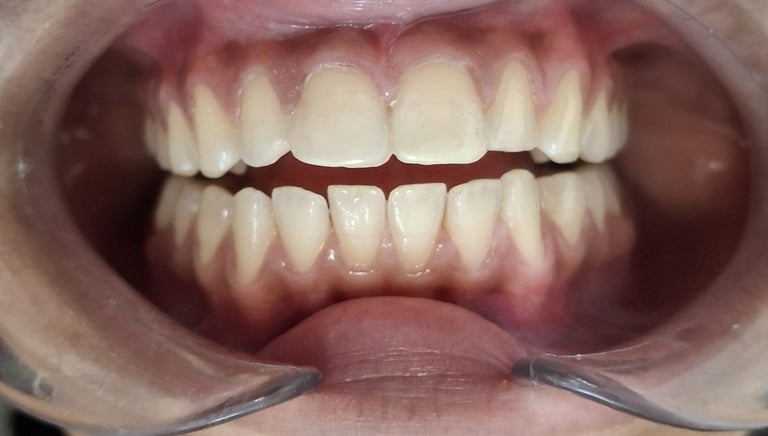

Professional Teeth Cleaning in Shyamal, Ahmedabad

Gentle, properly performed and tailored teeth cleaning for each person giving you comfort, safety and visible results. People from Shyamal and nearby areas of Ahmedabad visit our clinic for comfortable and very effective teeth cleaning.

Before

After

All images shown here are real teeth cleaning cases treated at our clinic with patient consent.

Professional teeth cleaning helps remove plaque, tarter, and surface stains that regular at home brushing can not.

At Shree Dental Care, teeth cleaning is performed gently with focus on patient experience, comfort and long term oral health.